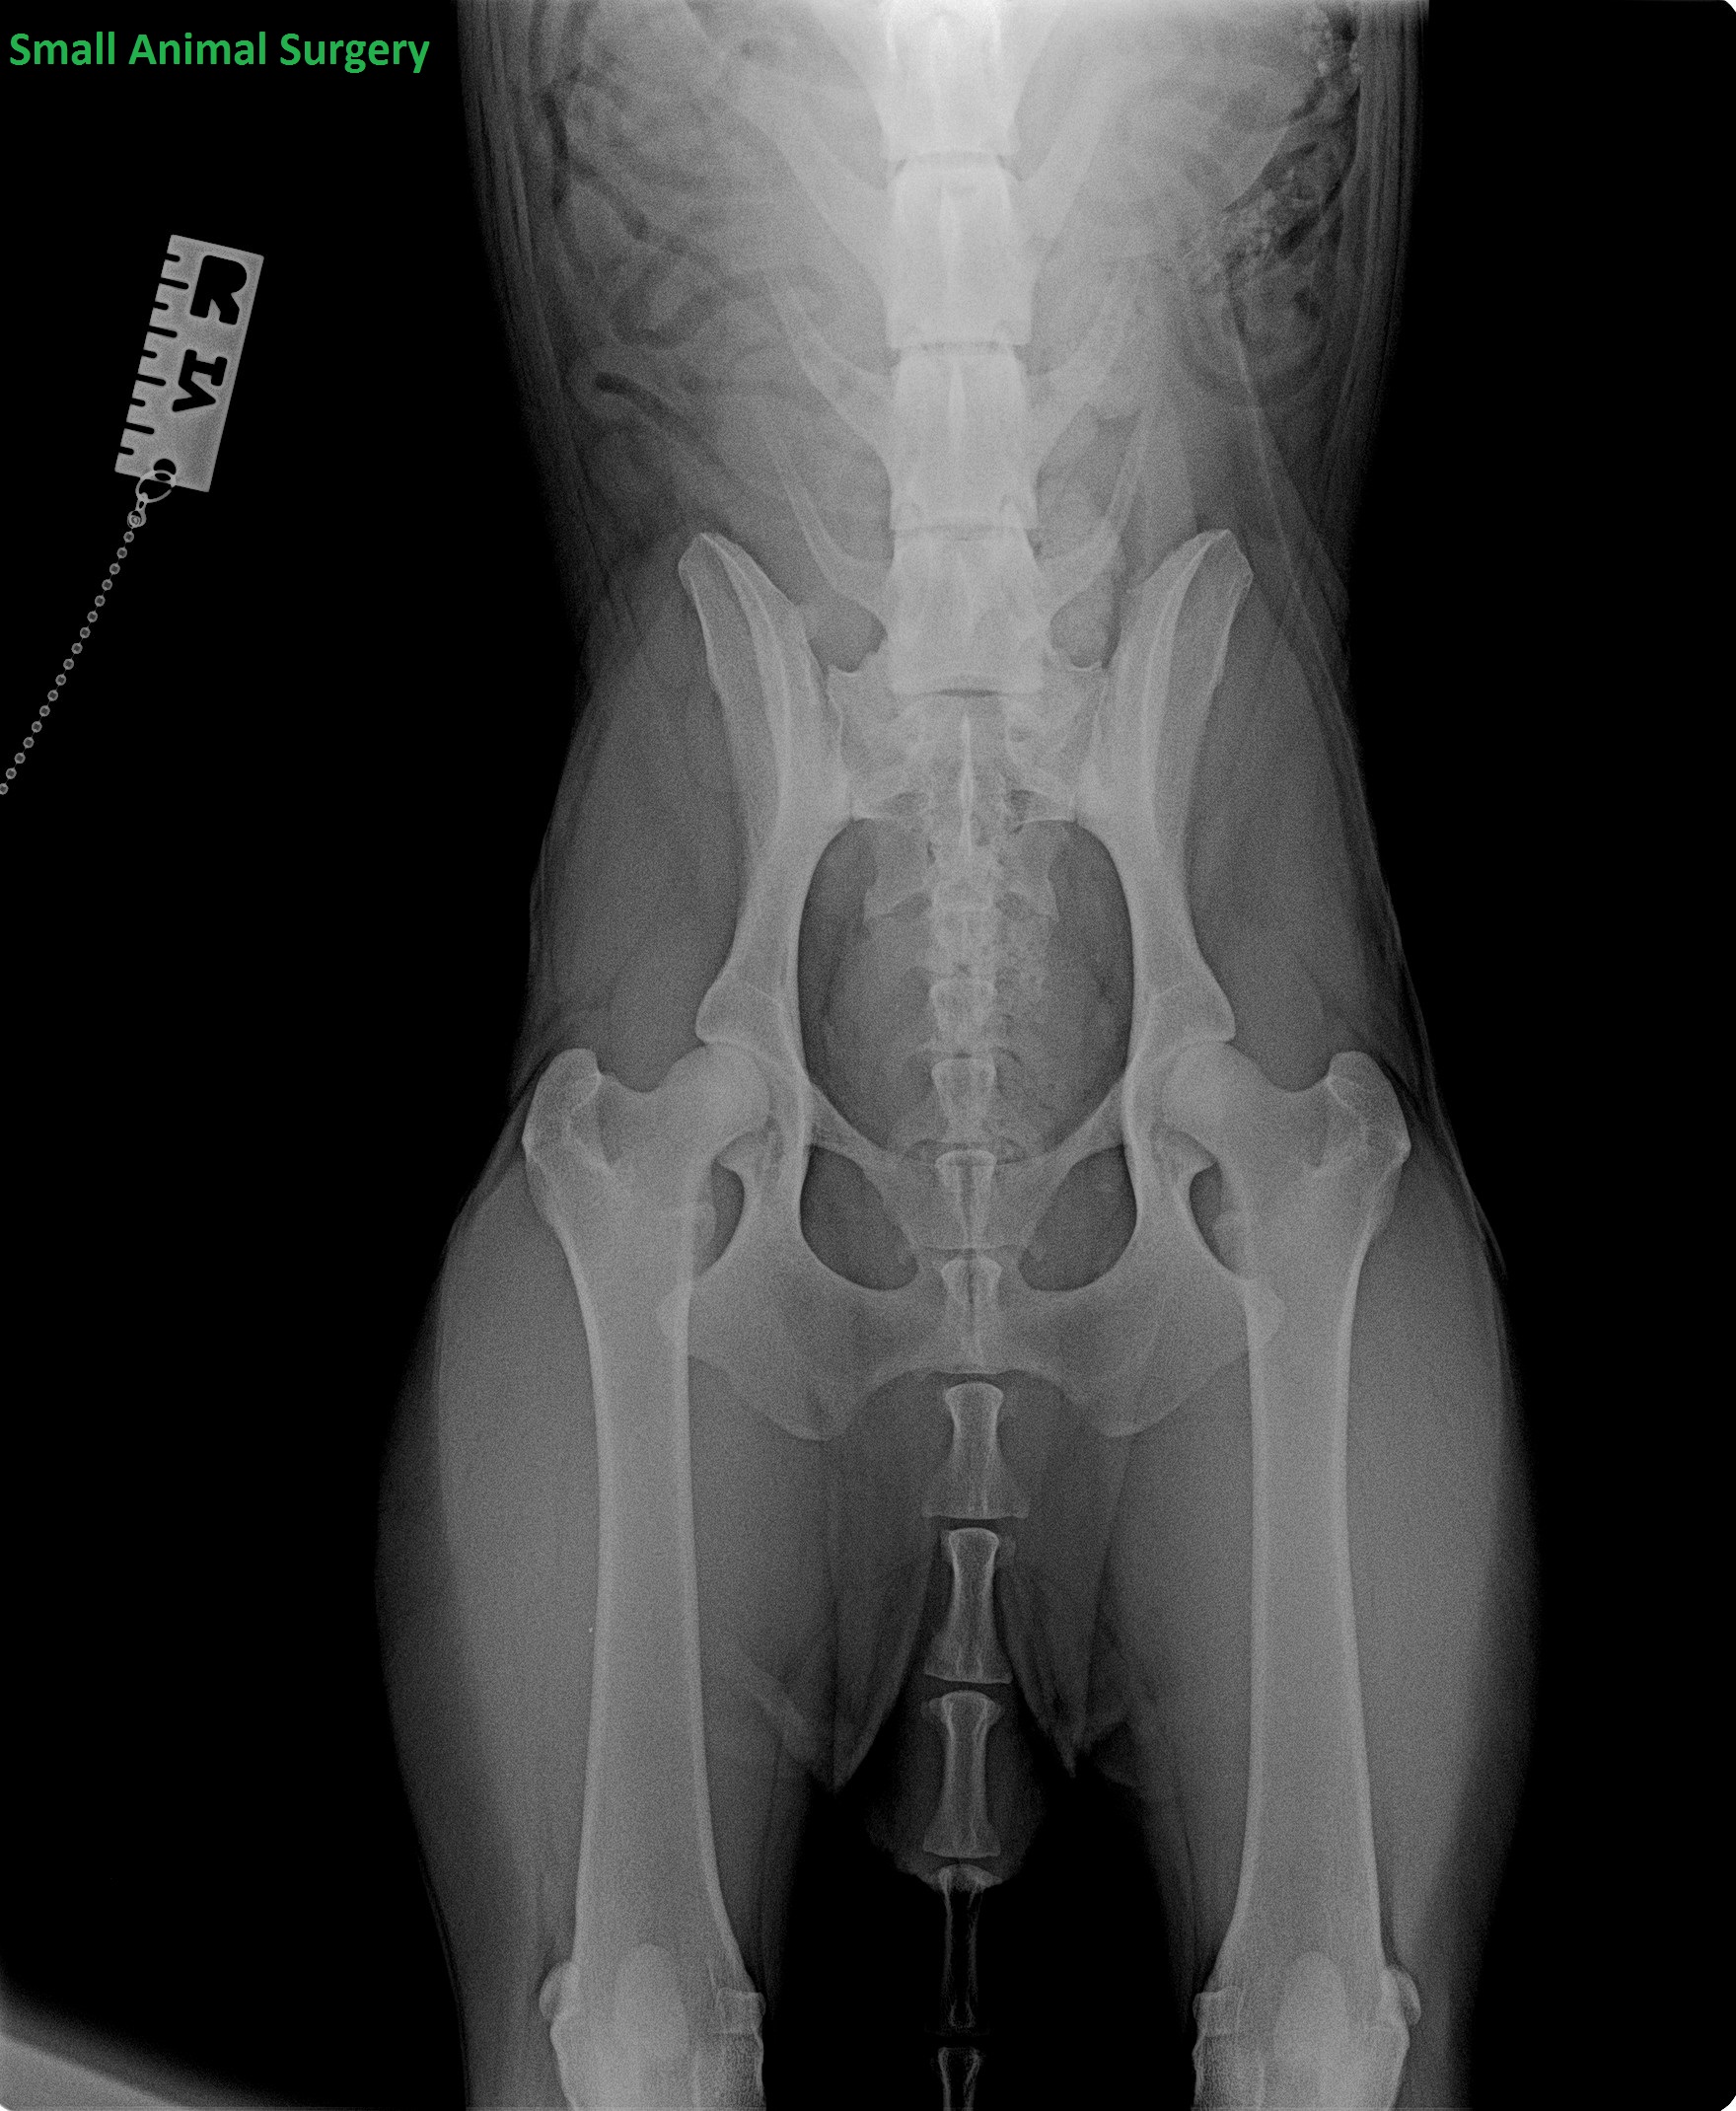

Έχει σημασία να είναι συμμετρική η ακτινογραφία;

Έχει ιδιαίτερη σημασία να είναι συμμετρική η ακτινογραφία για να έχουμε την πραγματική εικόνα των αρθρώσεων. Η ακτινογραφία είναι δισδιάστατη και το ζώο τρισδιάστατο άρα οποιαδήποτε κλίση έχει το ζώο προς τη μία ή την άλλη πλευρά τότε αλλάζει και η εικόνα των ισχίων. Το ένα θα δείχνει καλύτερο και το άλλο χειρότερο!!

Επισήμανση: η θέση της ουράς ΔΕΝ παίζει ρόλο στη συμμετρία της ακτινογραφίας

Σε αυτό το σημείο να παραθέσουμε ένα παράδειγμα που έχει ενδιαφέρον. Ιδιοκτήτης σκύλου Labrador ηλικίας 6 μηνών, σχεδόν πανικόβλητος, έρχεται στο ιατρείο με την απαίτηση ότι το ζώο του θέλει χειρουργείο για αποκατάσταση δυσπλασίας του ισχίου. Βγάζουμε ακτινογραφία να δούμε που βρισκόμαστε στην οποία όμως δεν έχουμε συμμετρία:

Σε ζώα που είναι σε κακή κατάσταση ακτινολογικά, ακόμα και να μην είναι συμμετρική η ακτινογραφία, δεν χρειάζεται να ταλαιπωρούμε το ζώο βγάζοντας και άλλες. Στο συγκεκριμένο παράδειγμα το ζώο είναι βαθμολογικά E όμως παρόλο που είναι μικρής ηλικίας λόγω της κακής κατάστασης του ισχίου οι χειρουργικές λύσεις είναι συγκεκριμένες: είτε εκτομής της κεφαλής του μηριαίου είτε ολική αντικατάσταση του ισχίου (επιλογή άλλου είδους χειρουργείου δεν υπάρχει καθότι είναι σχεδόν έξω το ισχίο!). Και για τις 2 όμως επεμβάσεις έπρεπε να περιμένει μήνες καθότι πρέπει σχεδόν να ολοκληρωθεί η ανάπτυξη για να γίνουν αυτές οι επεμβάσεις οπότε έως τότε έπρεπε να ακολουθηθεί φαρμακευτική αγωγή και διατήρηση σωστού σωματικού βάρους. Στους επόμενους μήνες με την αγωγή ο σκύλος δεν είχε καθόλου σχεδόν συμπτωματολογία και ακόμα έως και σήμερα, που ο σκύλος είναι 2.5 ετών, δεν έχει γίνει επέμβαση. Για του λόγου το αληθές: